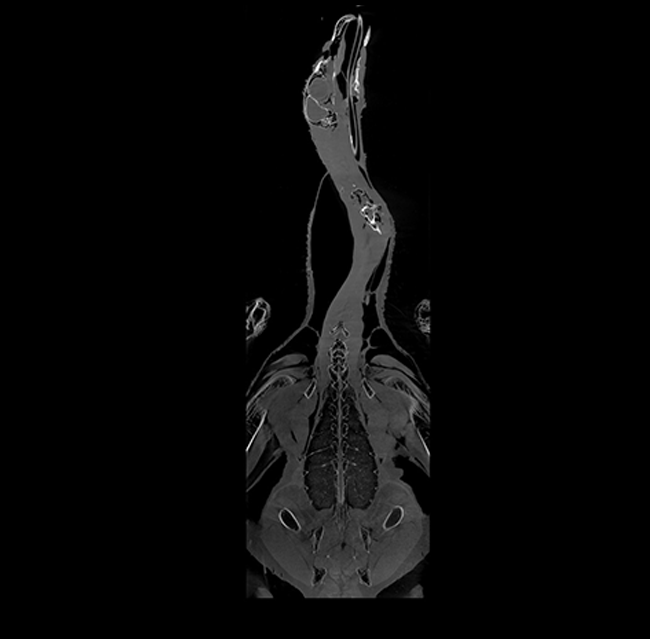

Our High Definition Volumetric Imaging (HDVI) technology is the most advanced form of Flat Panel CT technology. It delivers high-quality diagnostic imaging for both hard and soft tissues. This technology includes specific presets and customizable accessories designed for zoo animals.

High Definition Volumetric Imaging (HDVI) Computed Tomography and Fluoroscopy in one device.

Outstanding image quality in hard and soft tissues with a spatial resolution up to 100 μ.